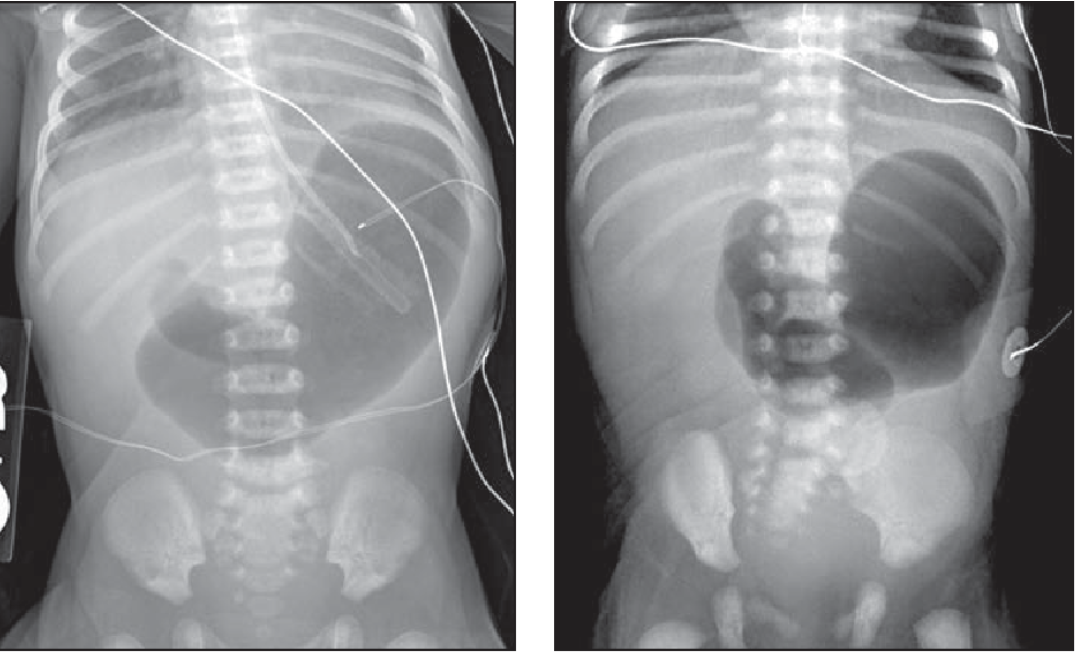

what does midgut volvulous show on imaging?

paucity of gas throughout with few scattered air-fluid levels

doppler shows abnormal relation of superior mesentric vessels to the superior mesenteric artery